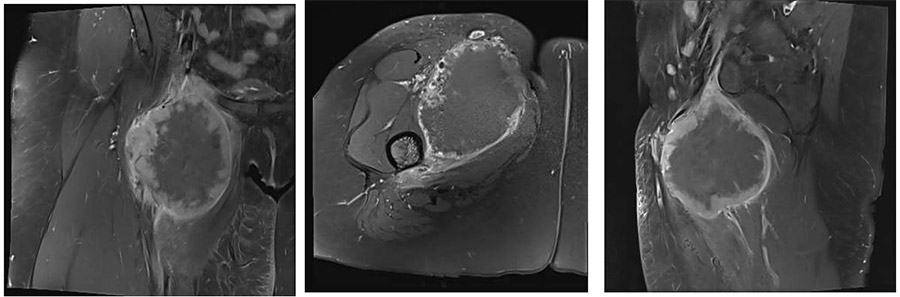

Ameliyat Öncesi: MR’da proksimal uyluk medialde femoral arter ven paketini çevreleyen düzensiz sınırlı, heterojen, mekezinde nekrozun eşlik ettiği yumuşak doku kitlesi görülmekte